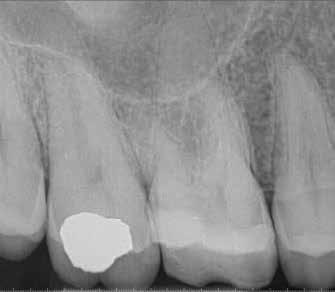

1. a–g. ábrák: A direkt pulpasapkázás lépései. Kiindulási bitewing-felvétel: A meglévő restaurátum közel helyezkedett el a pulpakamrához (a). Kiindulási periapicalis felvétel: Nincs periapicalis elváltozás fennállására utaló jel (b). A pulpaexpozíció (c). A vérzéscsillapítás céljából 20 másodpercen keresztül steril vattagombóccal történő kompressziót követően látható pulpaseb (d). A pulpasapkázás céljából behelyezett anyag, a széli részek tisztázása előtt készült felvétel (e). A röntgenárnyékot nem adó ideiglenes tömés behelyezése után készült felvétel (f). Az első ülés végén a röntgenárnyékot nem adó ideiglenes töméssel ellátott fogról készített röntgenfelvétel (g).

2. ábra: A hat hónapos kontroll alkalmával készített röntgenfelvételen vastag dentinhíd látható a pulpasapkázó anyag alatt.

3. ábra: A hároméves kontroll alkalmával készített röntgenfelvételen megfigyelhető a restaurátum pontos illeszkedése.

Esetbemutatás (1.)

Egy 35-éves férfi beteg akut ellátás céljából kereste fel rendelőnket. A jobb felső második kisőrlő (15) fogát érő hideg inge-

rekre jelentkező, rövid ideig tartó éles fájdalomra panaszkodott.

A diagnózisunk reverzibilis pulpitis volt. Periapicalis elváltozás jelenlétét nem vélelmeztük. A fogban lévő amalgámtömés eltávolítása során körülbelül egy 3 mm átmérőjű pulpaseb keletkezett a buccalis pulpaszarvnak megfelelően (1. a–g. ábrák) Mivel nem tapasztaltunk jelentős vérzést, és a diagnózisunk reverzibils pulpitis volt, ezért a direkt pulpasapkázás elvégzése mellett döntöttünk.

A kavitást 2,5%-os nátrium-hipoklorit oldattal fertőtlenítettük, majd sűrű konzisztenciájú kalcium-szilikát alapú anyagot (CeraPutty, Meta Biomed) készítettünk elő a direkt pulpasapkázás elvégzéséhez. Az első kezelés végén röntgenárnyékot nem adó ideiglenes töméssel (NexTemp LC, Meta Biomed) zártuk

az üreget annak érdekében, hogy a direkt pulpasapkázásra használt anyag megfelelő pozícióját radiológiailag ellenőrizni tudjuk. A második ülés során kompozit tömőanyagból (Ezfil, Meta Biomed) direkt adhezív restaurátumot készítettünk.

A kezelést követően a beteg tünetmentes volt. A kérdéses fog a kontrollvizsgálatok során végzett szenzibilitástesztekre fiziológiás reakciókat adott. A hat hónapos kontroll alkalmával készített röntgenfelvételen a sérülésnek megfelelően széles dentinhidat észleltünk (2. ábra). A restaurátum a hároméves kontroll során is megfelelőnek bizonyult (3. ábra)